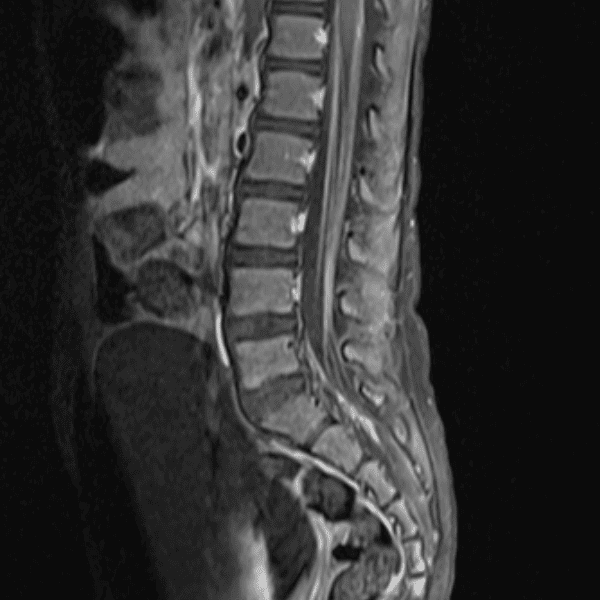

Simulates call by including subtle or difficult cases and some normals.

35 cases